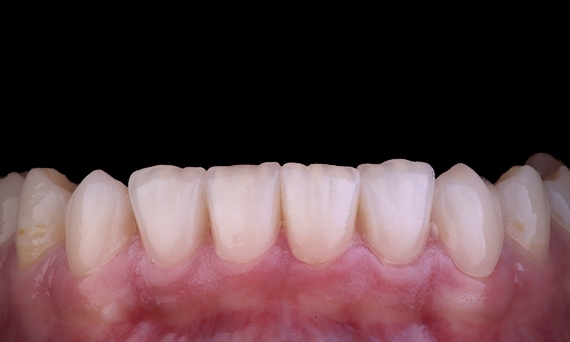

Es bastante común observar las grietas y fracturas asociadas con las restauraciones de amalgama, particularmente a medida que aumentan de tamaño, ya que son restauraciones “sin unir”. Muchos de estos dientes tienen su estructura comprometida y el método ideal para su restauración es el enfoque biomimético adhesivo. Como parte de un plan de tratamiento más integral, se planificó que este cuadrante tuviera dos incrustaciones dentales onlay de cerámica indirecta. El primer y el segundo molar se restauraron en una sola visita usando CEREC Tessera, un disilicato de litio avanzado.

Dr. Yo-Han Choi, Sídney, Australia